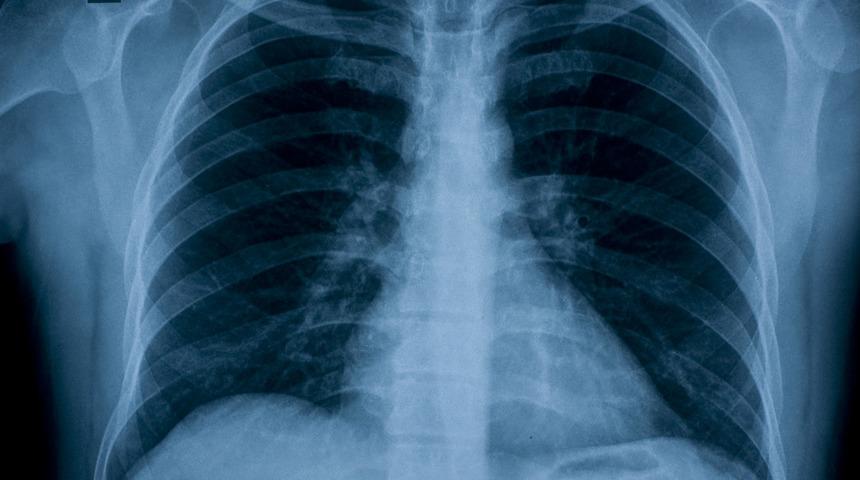

Solunum sisteminin en önemli organları olan akciğerler, havada bulunan çeşitli toksinler, hava kirliliği sebebiyle varlık gösteren mikroorganizmalar, özellikle aktif veya pasif sigara içiciliğinden kaynaklanan partiküller, toz ve alerjenlerden etkilenerek zayıflar.

Şu ana kadar sözünü ettiğimiz tüm doğal yöntemler, akciğeri filtreleme görevi üstlenen balgamın vücuttan sökülüp atılması konusunda fayda sağlamaktadır. Balgamın sağlıklı bir renk ve dokuya kavuşması ve yeniden fark etmediğiniz bir salgı kıvamına gelmesi, akciğerlerinizin de temizlenmesi anlamına gelir.